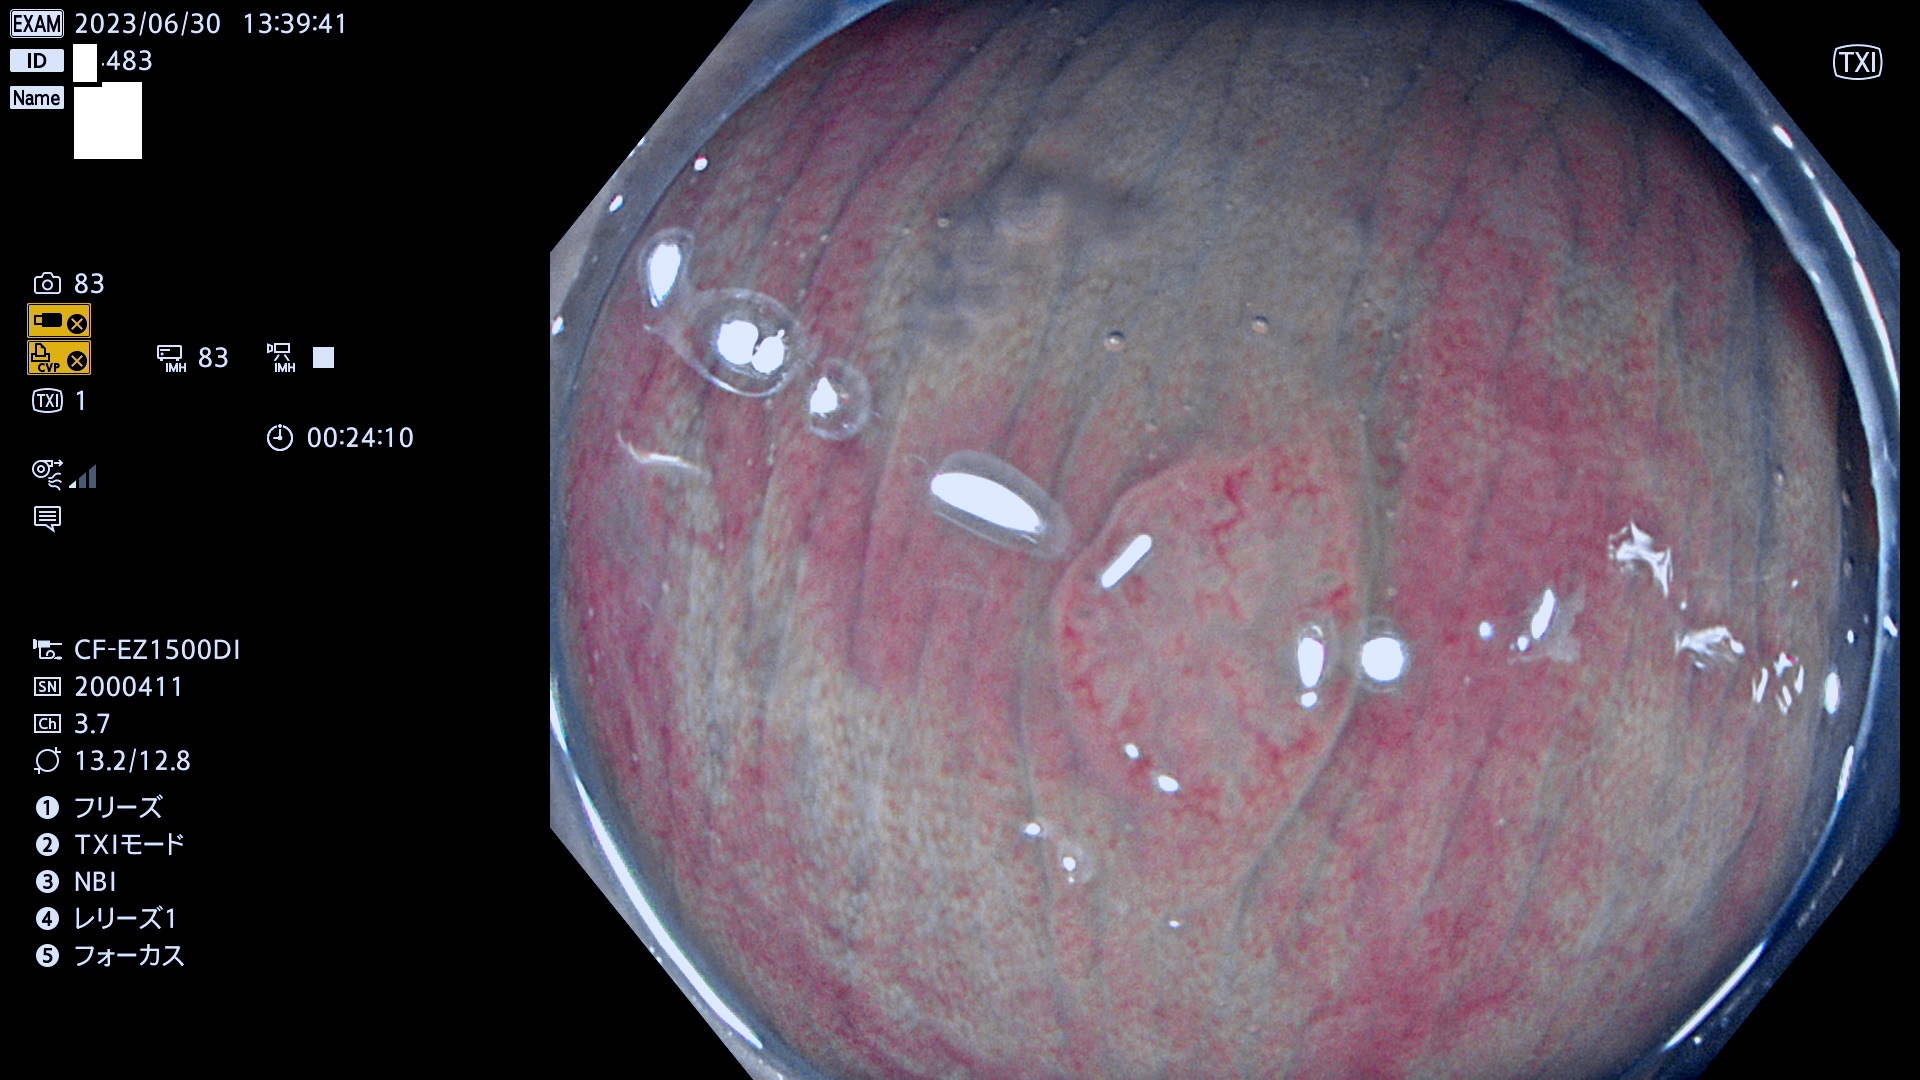

「表面型腫瘍」の中で、完全に平坦な物をUb、陥凹している物をUcと呼びます。平坦隆起型(Ua)よりも、発見が難しく危険な病変です。このタイプの発見率は「腺腫発見率」よりも、遥かに重要な意義があります。

抽出の対象期間 2023年6月29日(木)〜7月2(日)の4日間(48件の検査)8件